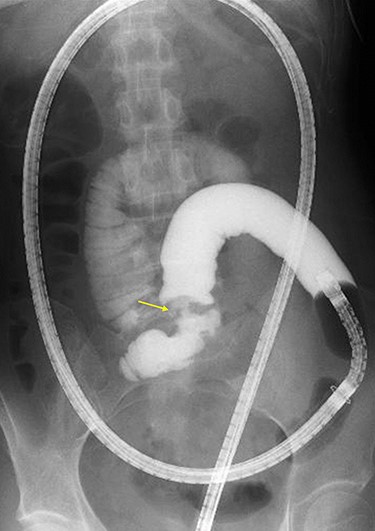

A 45-year-old woman was admitted with recurrent abdominal pain. She had no significant past medical history. Physical examination showed mild tenderness in the lower abdomen. Laboratory findings were within normal limits, except for serum carbohydrate antigen 19-9 (58 U/mL). Computed tomography (CT) scan showed a continuous lesion to the ileum with contrast enhancement (Fig. 1). Retrograde double-ballon enteroscopy showed an ulcerated lesion at 160 centimeters from the ileocecal valve, and biopsy showed well-differentiated adenocarcinoma (Fig. 2). An enteroscopy-assisted contrast study revealed intestinal stenosis involving a Meckel’s diverticulum (Fig. 3). Based on these findings, we diagnosed adenocarcinoma in a Meckel’s diverticulum preoperatively. Intestinal resection with lymph node dissection was performed. Operative findings showed that the tumor invaded the Meckel’s diverticulum 160 centimeters from the ileocecal valve. No findings of abdominal dissemination were observed (Fig. 4). Histological examination of the resected specimen revealed a well-differentiated adenocarcinoma, interrupted by ectopic gastric mucosa (one side shown, Fig. 5a.).

Double-ballon enteroscopy-assisted contrast study demonstrating intestinal stenosis involving a Meckel’s diverticulum (arrow).